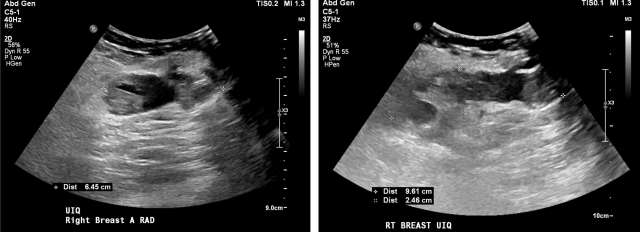

• US: Complicated hypoechoic or isoechoic fluid collection. Mobile debris within the fluid collection and hypervascularity of the adjacent breast tissue are characteristic, Figure 1.7

Case: Post-Surgical Fluid Collections Figure 1

Figure 1 - Ultrasound demonstrates septated, heterogenous fluid collection with surrounding hypervascularity. The patient was 3 weeks status post mastectomy and presented with breast redness and tenderness. The collection was drained, with cultures growing staph aureus.